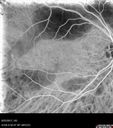

Multifocal Vitelliform Macular Dystrophy453 views58 year old female with mild vision loss - 20/20 OU - extensive testing has shown no cancer. Case of Karina Findlay, MD